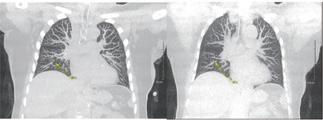

Imaging Software Aids Lung Diagnosis in Patients Allergic to Medical Contrast Dye

For up to 30% of patients who cannot use medical contrast dye due to allergies or other health conditions, diagnosing critical lung issues like pulmonary embolism can be delayed. This is because non-contrast dye imaging methods are less accurate and typically take longer to administer. Now, researchers at Corewell Health (Southfield, MI, USA; www. corewellhealth.org) have developed new imaging software to address this widespread challenge, offering such patients a more reliable and quicker diagnostic alternative. The software, known as CT-Derived Functional Imaging, or CTFI, utilizes advanced computed tomography technology and has shown potential in minimizing radiation exposure to healthy lung areas adjacent to tumors during treatments. Additionally, it has proven effective in detecting pulmonary embolism by identifying changes in blood mass through a simple non-contrast CT scan during inhalation and exhalation.